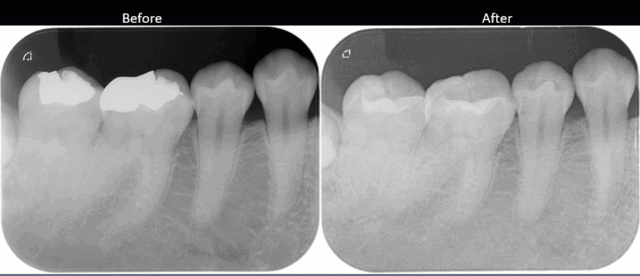

before

after

| 通院回数・期間 | 1回〜3回 |

| 処置内容 | 右下6番(セラミックインレー)7番(ダイレクトボンディング)を治療 |

| 今回の施術費用 | ¥33,000〜110,000 |

歯を削る量を少なくできる。歯に直接詰め物をつけることができる。ピッタリ詰めれる。

奥歯で器具が入りにくい場所や、大きい虫歯治療には適応できない場合がある。